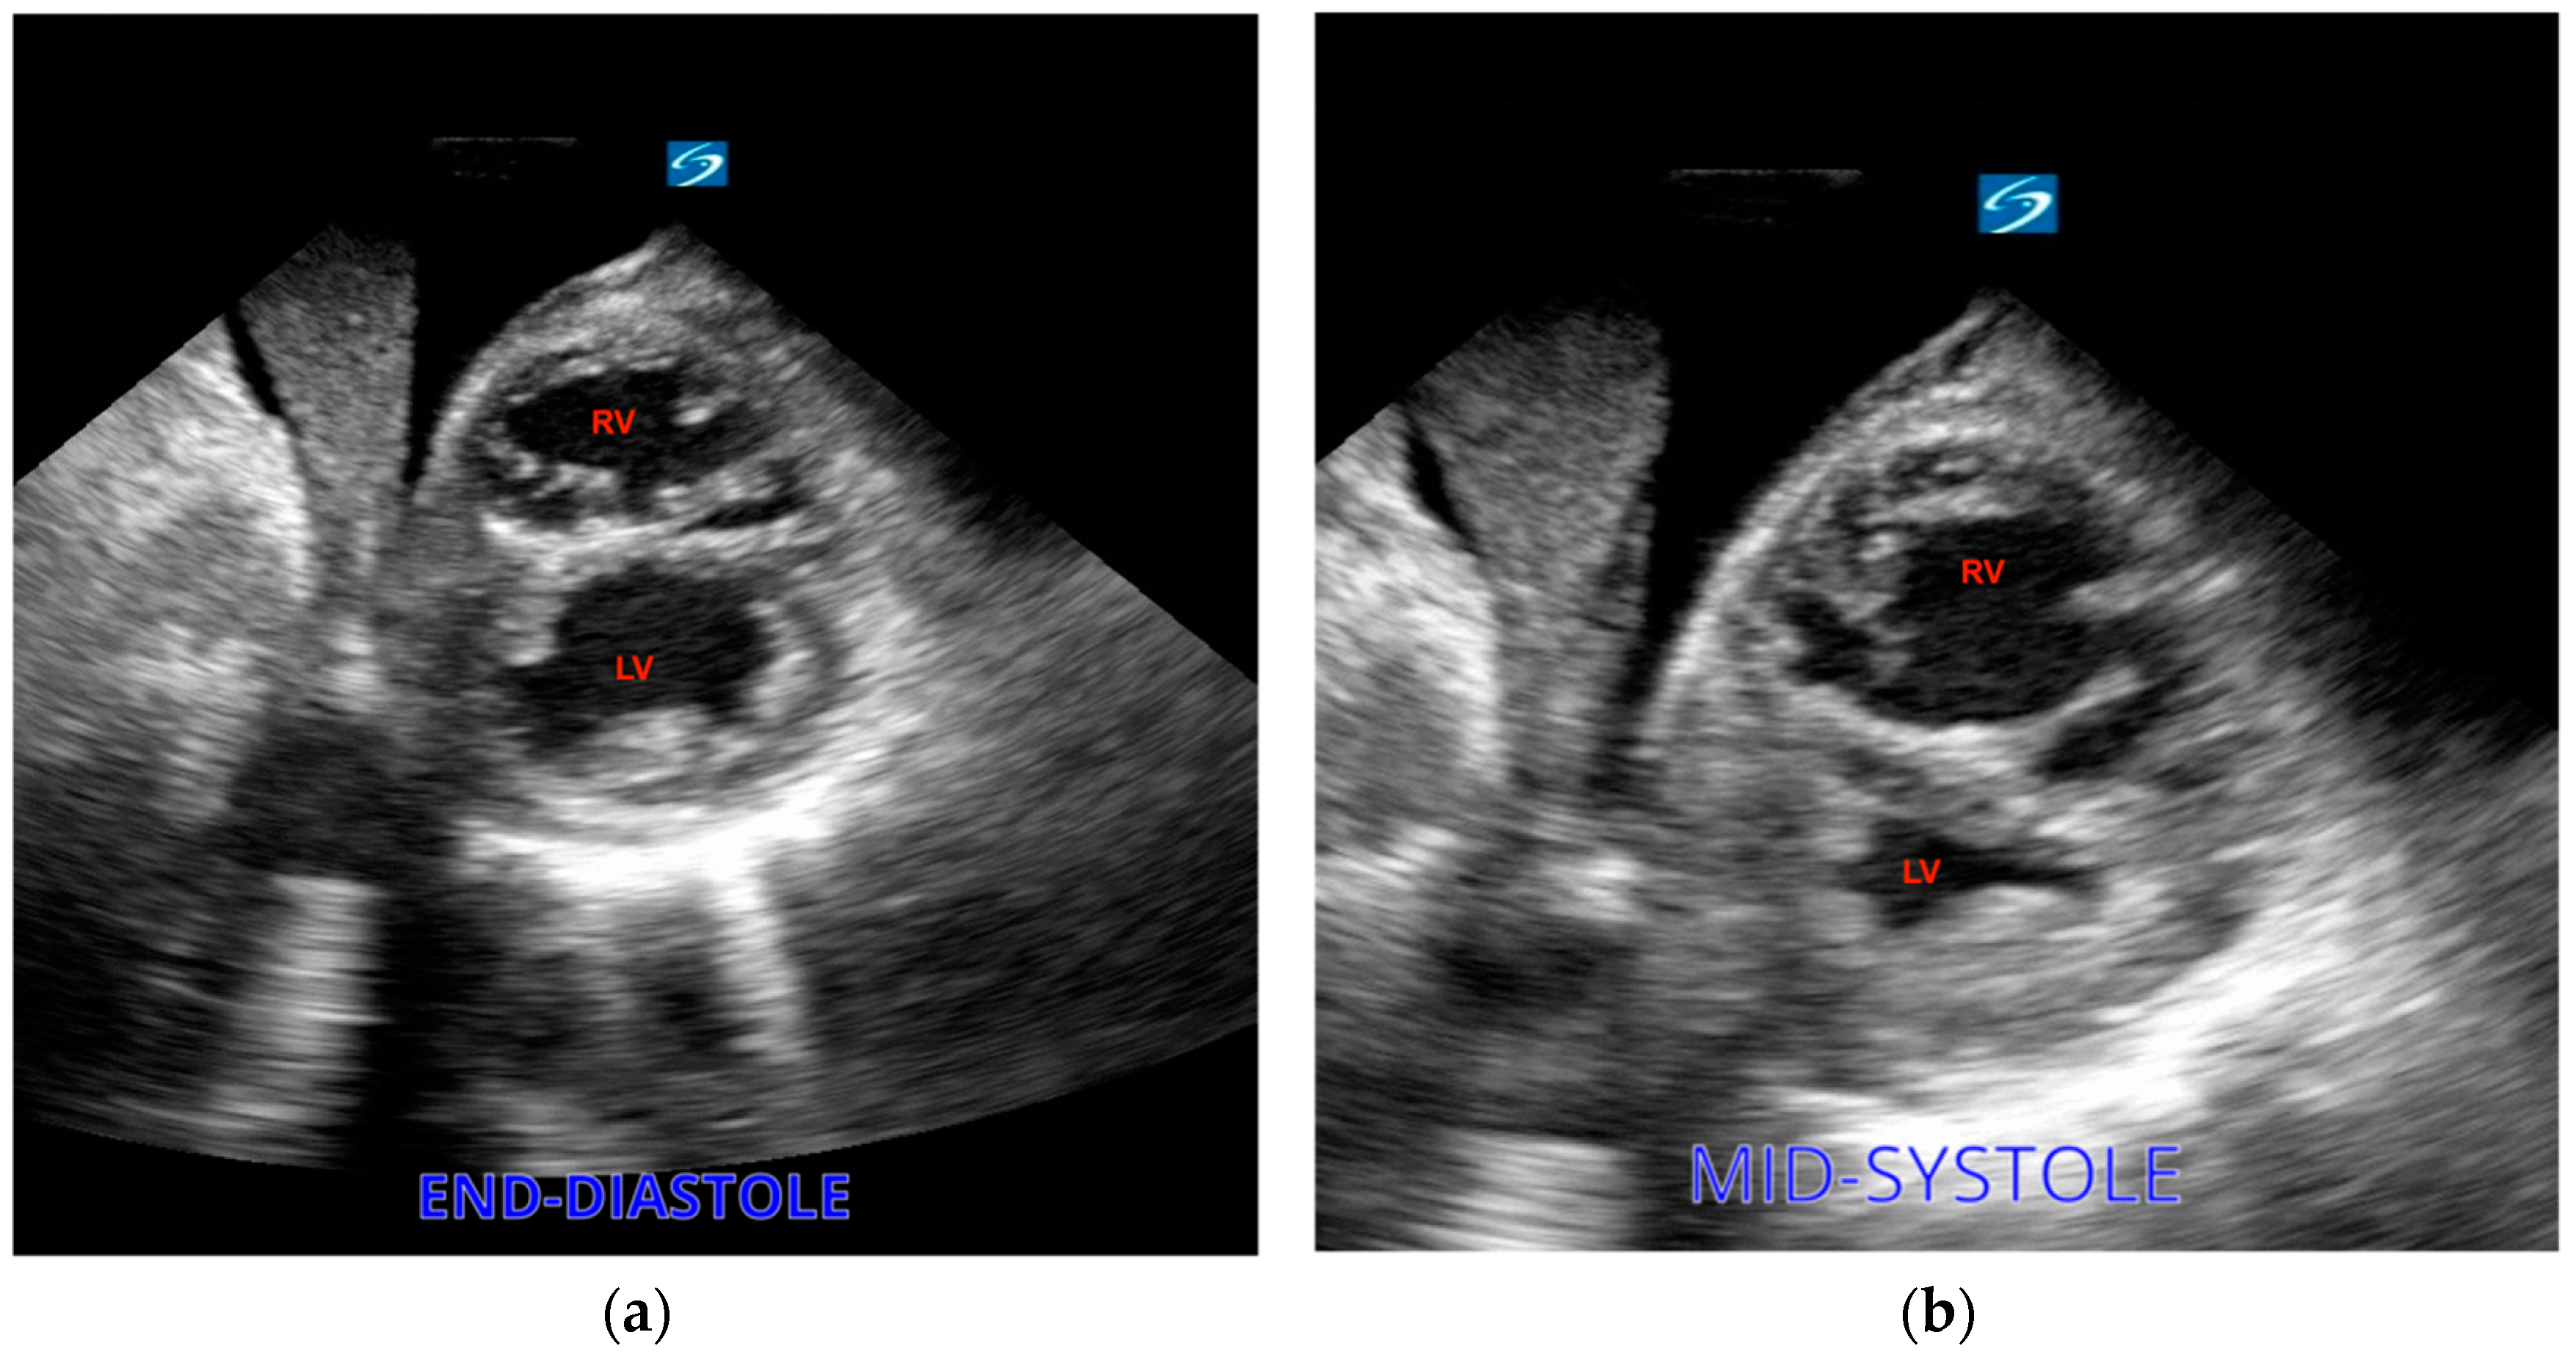

Cardiac arrest can result from hypovolemia due to decreased intravascular volume and extensive vasodilation. Hemorrhagic shock is the primary cause of death in this setting, especially in trauma patients [30]. While reduction in blood volume might be evident in traumatized patients, detecting the origins of internal bleeding presents a more considerable diagnostic hurdle, which can be addressed by employing ultrasound. The evaluation of size and function of the ventricles can aid in determining whether there is reduced cardiac filling due to decreased blood volume. Reduced left ventricular size might suggest hypovolemia [31]. The left ventricle might be hyperdynamic, with obliteration of the LV volume at the end of systole (Figure 5).

Figure 5.

Left ventricle (arrow) during diastole (a) and at the end of systole, obliterated and suggesting hypovolemia (b).

Dilatation of the right ventricle in opposition to a small left ventricle is a typical right heart strain sign that can be seen on an echo and provides clues for the presence of PE. The diagnosis of dilation relies on a comparison between the diameters of the RV and LV at the end of diastole. A normal relationship is defined as 0.6:1 and can be evaluated via an apical four-chamber view, while a ratio of 1:1 is diagnostic of RV dilatation. Nonetheless, the association between RV dilatation and PE can be weak, given the fact that patients with cardiac arrest commonly present RV dilatation, particularly in cases where resuscitation efforts extend in duration [39]. As another sign of right heart strain, the right ventricle can present in a D shape as visualized in a parasternal short-axis view (Figure 7. Less frequently, a clot can be identified as a direct sign of PE [40]. In addition, as mentioned above, some protocols include scanning for deep vein thrombosis as an indicator of pulmonary embolism during arrest [41].

Figure 7.

(a) Severe right ventricular dilation showing a D-shaped RV. (b) The left ventricle (LV) is underfilled.